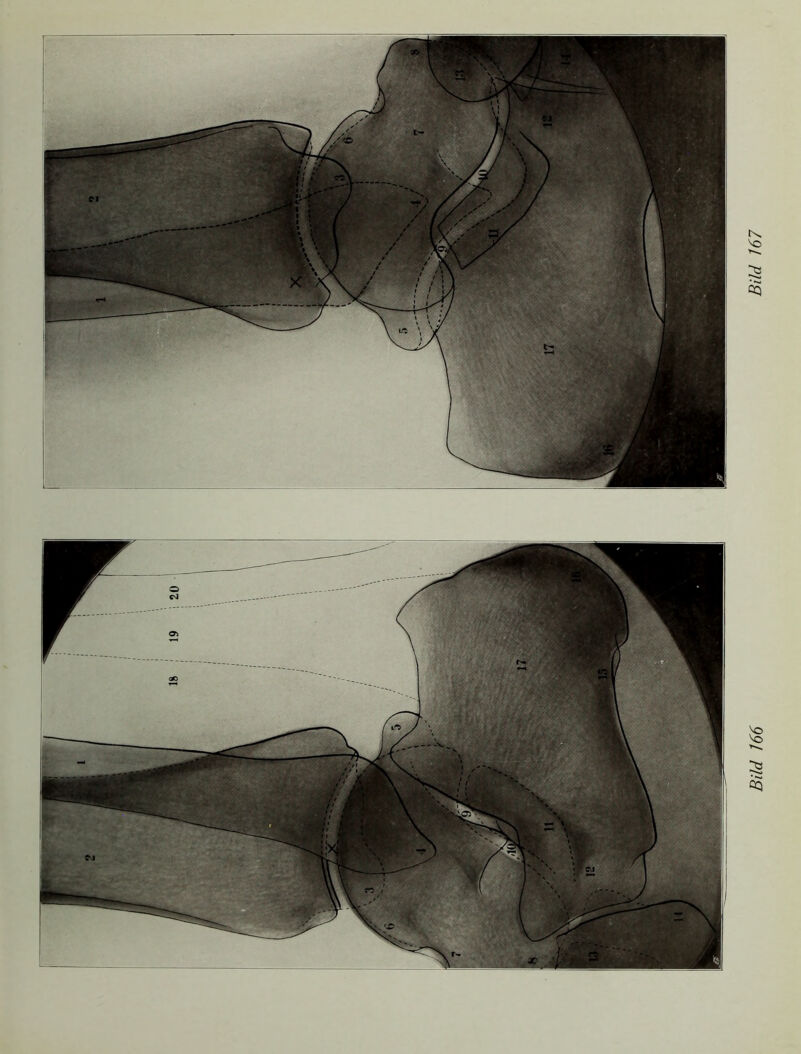

Atlas typischer Röntgenbilder vom normalen Menschen : ausgewählt und erklärt nach chirurgisch-praktischen Gesichtspunkten, mit Berücksichtigung der Varietäten und Fehlerquellen, sowie der Aufnahmetechnik / von Rudolf Grashey.

Credit: Atlas typischer Röntgenbilder vom normalen Menschen : ausgewählt und erklärt nach chirurgisch-praktischen Gesichtspunkten, mit Berücksichtigung der Varietäten und Fehlerquellen, sowie der Aufnahmetechnik / von Rudolf Grashey. Source: Wellcome Collection.